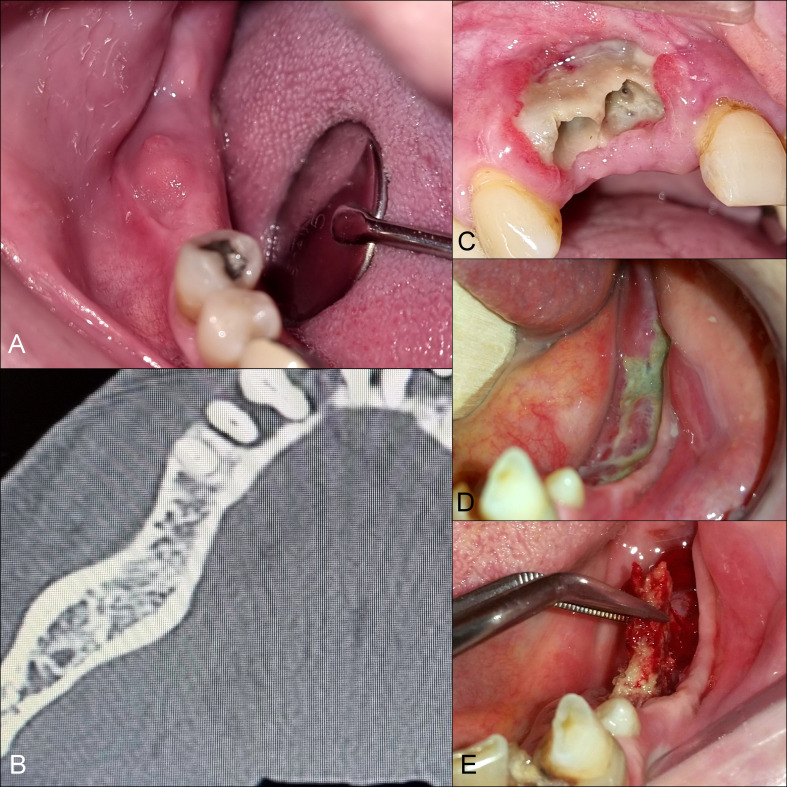

Abstract Image